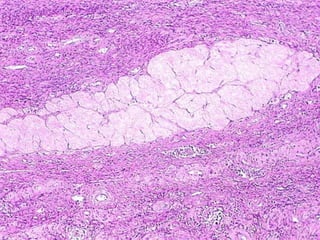

Adenocarcinoma of the Endometrium

=

Carcinoma of the Uterus

ADENOCARCINOMA

of the ENDOMETRIUM

• Papillary, Polypoid

• Clear Cell

• Adeno-Squamous

• Mucinous

• Serous

• Preceded by hyperplasia (EIN), dysplasia

• Estrogenic, DES effects

• Ass. w.: obesity, diabetes, hypertension, infertility

• Stromal “sarcomatous” conditions can co-exist,

i.e., “adenosarcoma”

GRADING and STAGING

• GRADING

– 1, 2, 3

– Well, Moderate, Poor

• STAGING

– (I) Corpus

– (II) Corpus + Cervix

– (III) Beyond uterus,

but inside true pelvis

– (IV) Outside true

pelvis or involving

bladder or rectal

mucosa